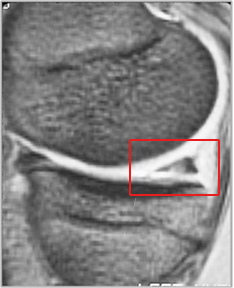

She presented to us with the MRI seen below. The red box on the MRI is over the medial meniscus cartilage. The MRI documents a chronic meniscus degenerative tear which had failed to respond to a partial meniscectomy. The options at this time when she presented to us were to repeat the meniscectomy. However, given the fact that it had already failed this did not seem to be a likely successful course of action. Therefore we planned to do a meniscus reconstruction where we would use a collagen scaffold as a regeneration template to regrow the missing meniscal tissue and therefore provide the shock absorber that her knee so clearly needed.

MRI (on right - a side view) revealed a tear of the posterior horn of the medial meniscus with inferior surface extension. MRI's are digital 'slices' through the body - this slice is from the side through the area of the meniscus at the back o the knee - the triangular bit in te red box is a cross section of the meniscus there - you can see that there is an interruption of the density of the structure.